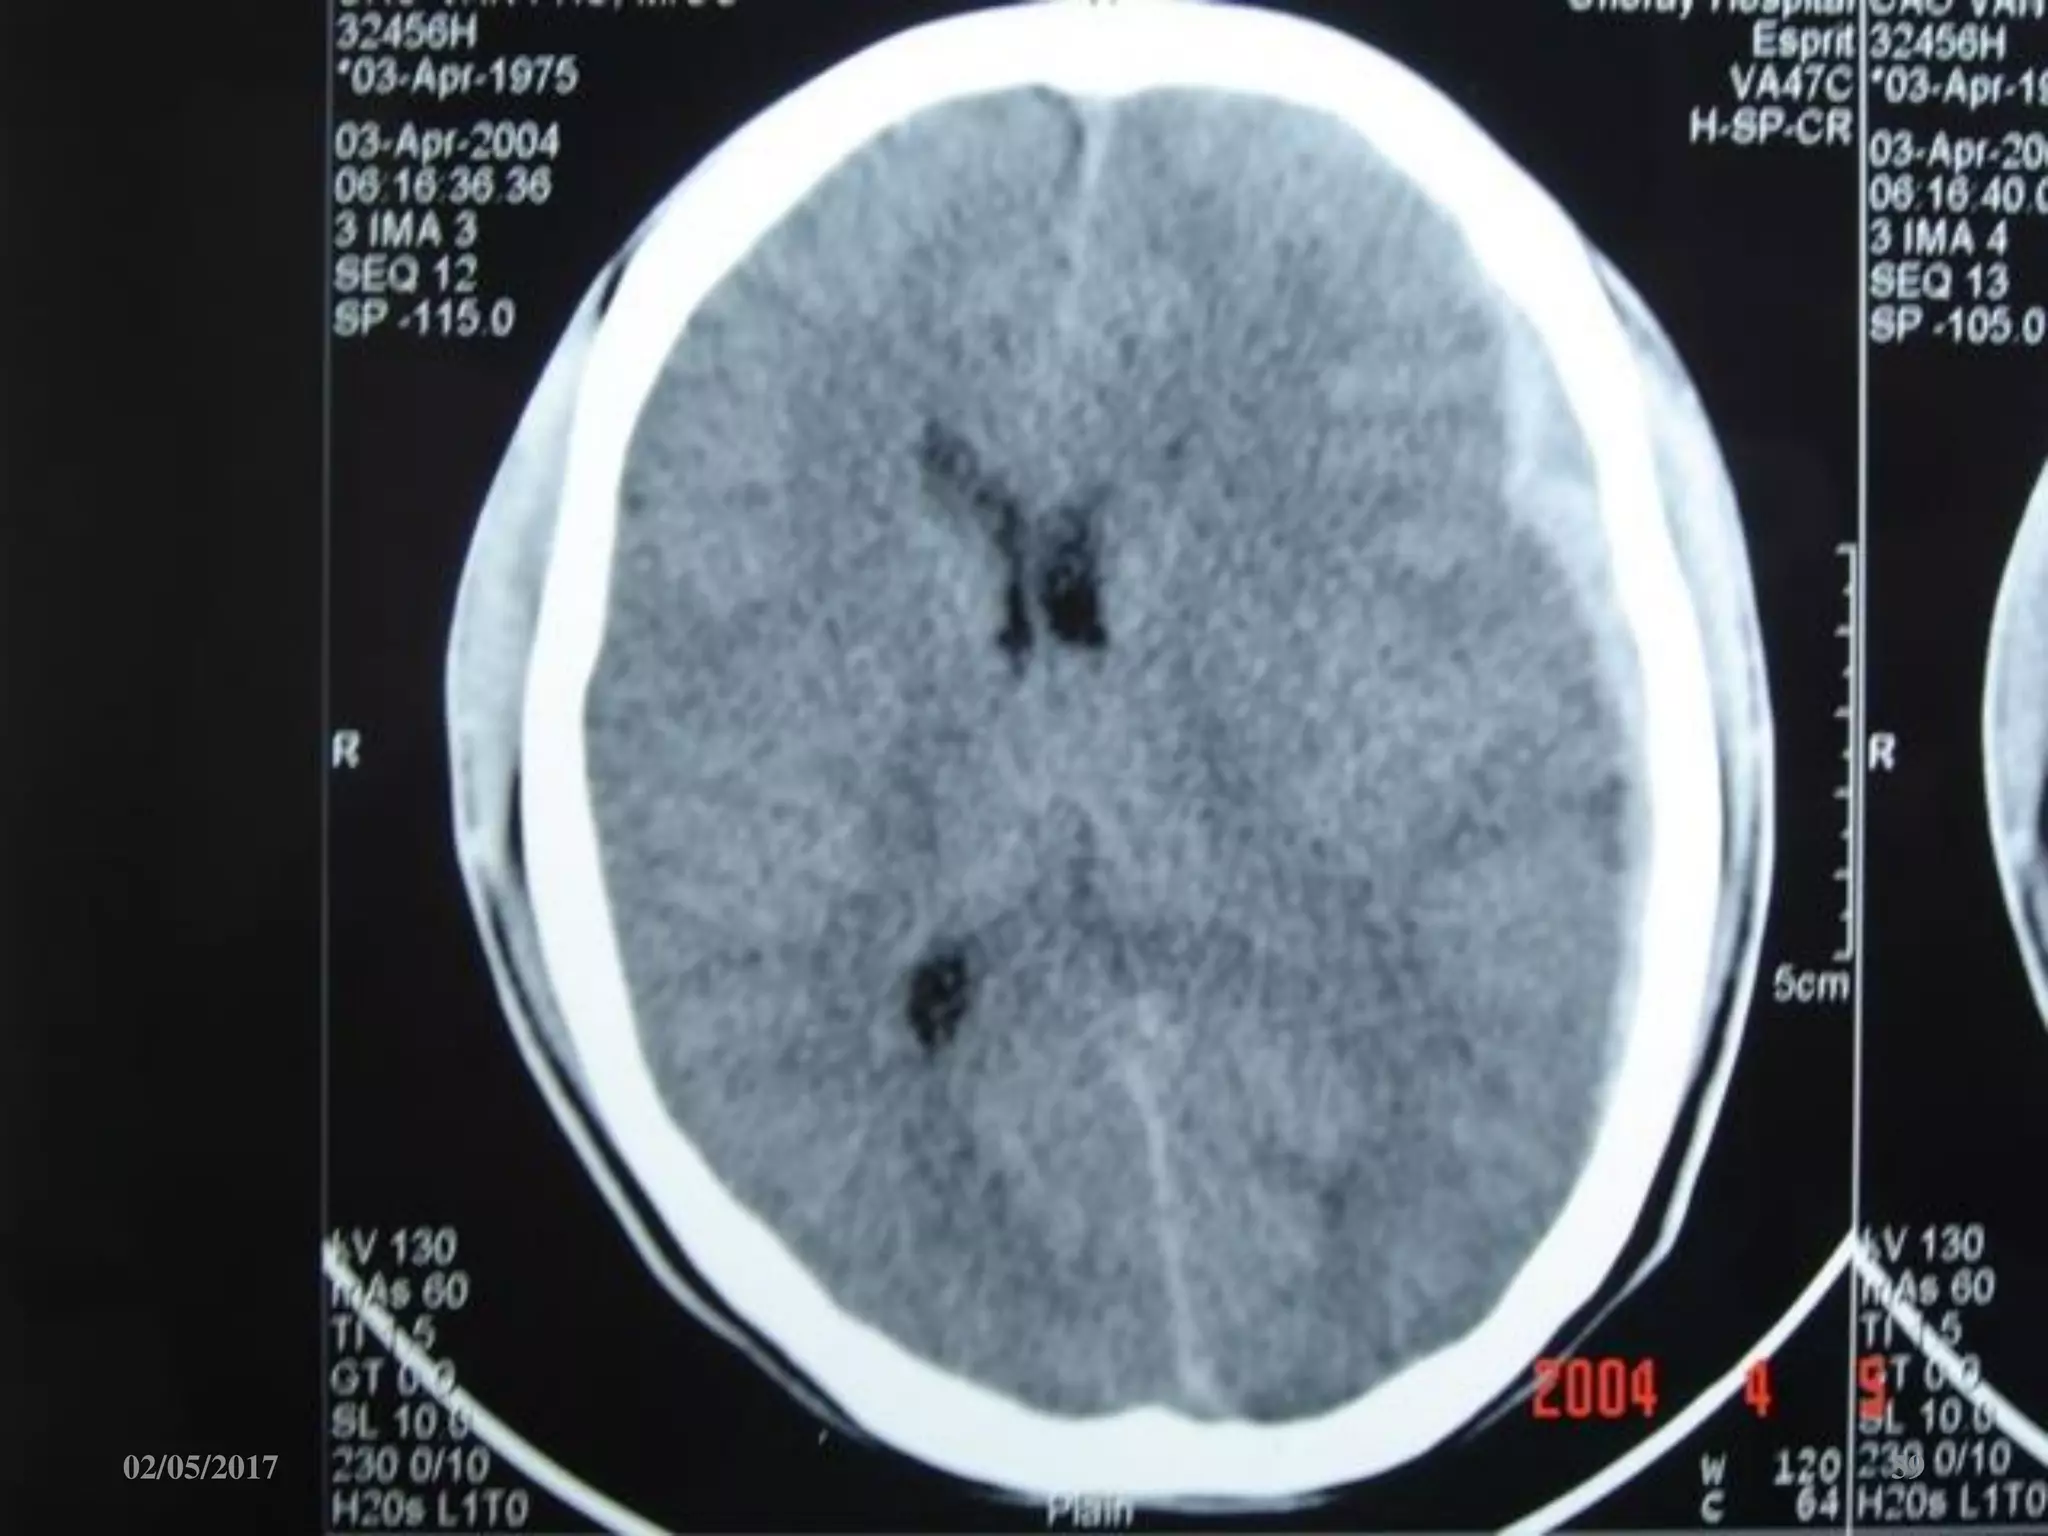

Máu tụ trong não

• Vị trí: trán, thái

dương, đỉnh, chẩm.

• Hình ảnh tăng đậm

độ trong tổ chức não

02/05/2017 60